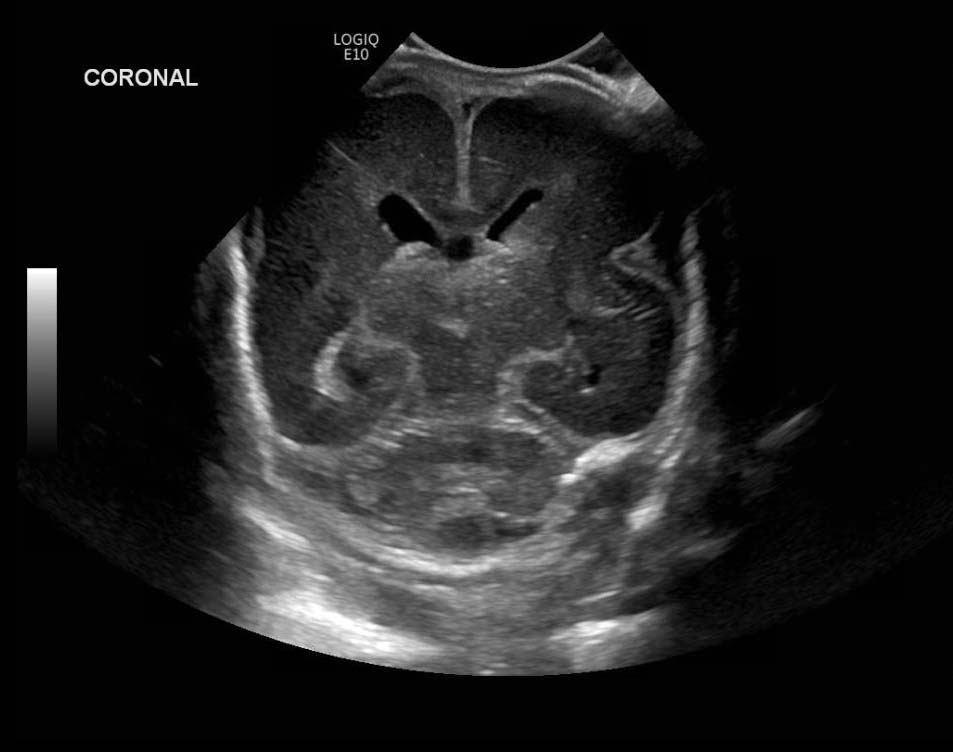

Age: 4 days (born at 24 weeks)

Sex: Male

Indication: Evaluate for germinal matrix hemorrhage

Grade 2 germinal matrix hemorrhage

Sample ReportLeft germinal matrix hemorrhage involving the caudothalamic groove and layering in the occipital horn of the left lateral ventricle without hydrocephalus (grade 2).

No abnormal brain parenchymal echogenicity or extra-axial collections.

Premature sulcation pattern.